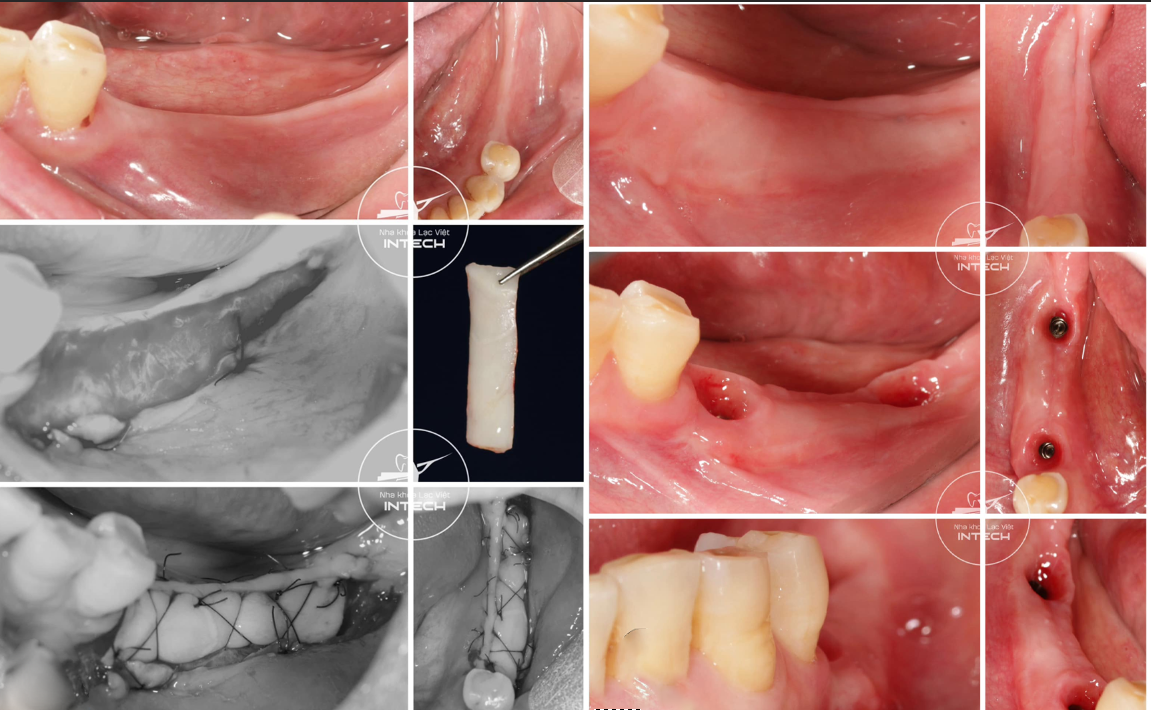

Ngoài ra, tại nha khoa Lạc Việt Intech, đội ngũ bác sĩ và cơ sở vật chất đảm bảo đủ điều kiện để thực hiện các phương pháp cấy ghép, thủ thuật phức tạp như cấy ghép tức thì, giải pháp phục hình cá nhân hóa DCT, ghép lợi...

Một ca phục hình cấy ghép Implant tức thì kết hợp ghép xương, được thực hiện đúng quy trình và đảm bảo an toàn tại Nha khoa Lạc Việt Intech

Thủ thuật ghép lợi trước khi cấy ghép Implant được thực hiện an toàn, chính xác tại nha khoa Lạc Việt Intech

Trường hợp mất răng hàm được nha khoa Lạc Việt Intech điều trị bằng phương pháp cá nhân hóa DCT